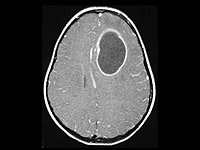

Descubren cómo saber si una persona en estado vegetativo tiene conciencia

El sistema inmunológico y la terapia genética erradican un tumor cerebral